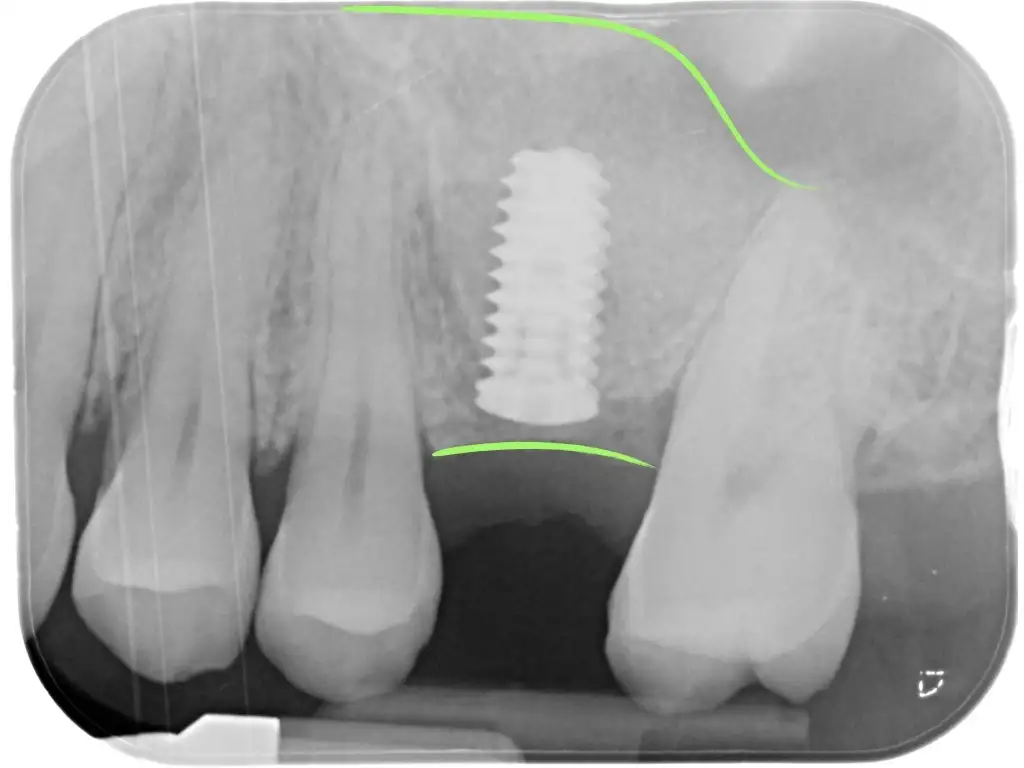

Fra le tecniche rigenerative è quella che probabilmente è necessaria più spesso. Al di sopra dei molari e premolari superiori è presente il seno mascellare. Questa è una cavità che, come gli altri seni paranasali, è vuota e piena d’aria (quando in salute), coperta da una sottile mucosa e in comunicazione con il naso.

E’ una cavità abbastanza ampia e spesso a diretto contatto con le radici dei molari. Quando un dente posteriore viene perso capita spesso che l’osso rimanente sia molto poco in altezza e impedisca di posizionare un impianto di lunghezza sufficiente.

In questi casi si può intervenire sollevando la membrana che copre il pavimento del seno mascellare, inserendo il biomateriale e fissando (nella grande maggioranza dei casi) già l’impianto. Tutto ciò sarà fatto in un unico intervento.

L’accesso al seno mascellare potrà essere dalla parete laterale (grande rialzo) nei casi più complessi o addirittura attraverso il piccolo foro realizzato per posizionare l’impianto in modo ancora più mininvasivo (mini-rialzo).

Il seno mascellare fa part dei seni paranasali, si trova sopra le radici dei denti posteriori. Quando mancano i denti molto spesso l’altezza ossea è insufficiente a posizionare un impianto